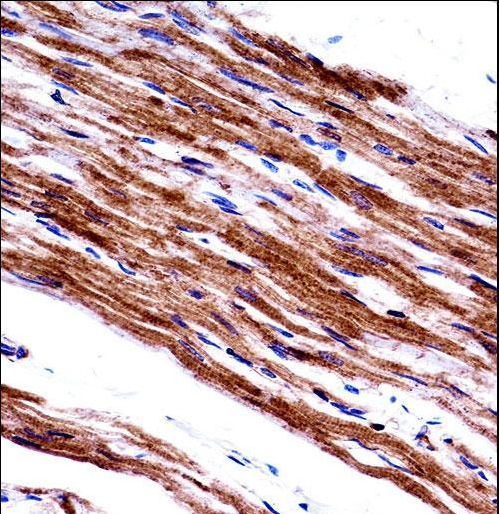

- Experimental details

- MYL9 Antibody immunohistochemistry of formalin-fixed and paraffin-embedded human heart tissue followed by peroxidase-conjugated secondary antibody and DAB staining.